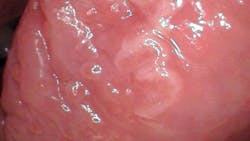

Patient: 77-year-old male

- 6 mm x 8 mm white leukoplakic lesion

- Lesion slightly corrugated with irregular borders

- Not painful to palpation or touch

- Located on left lateral border of the tongue